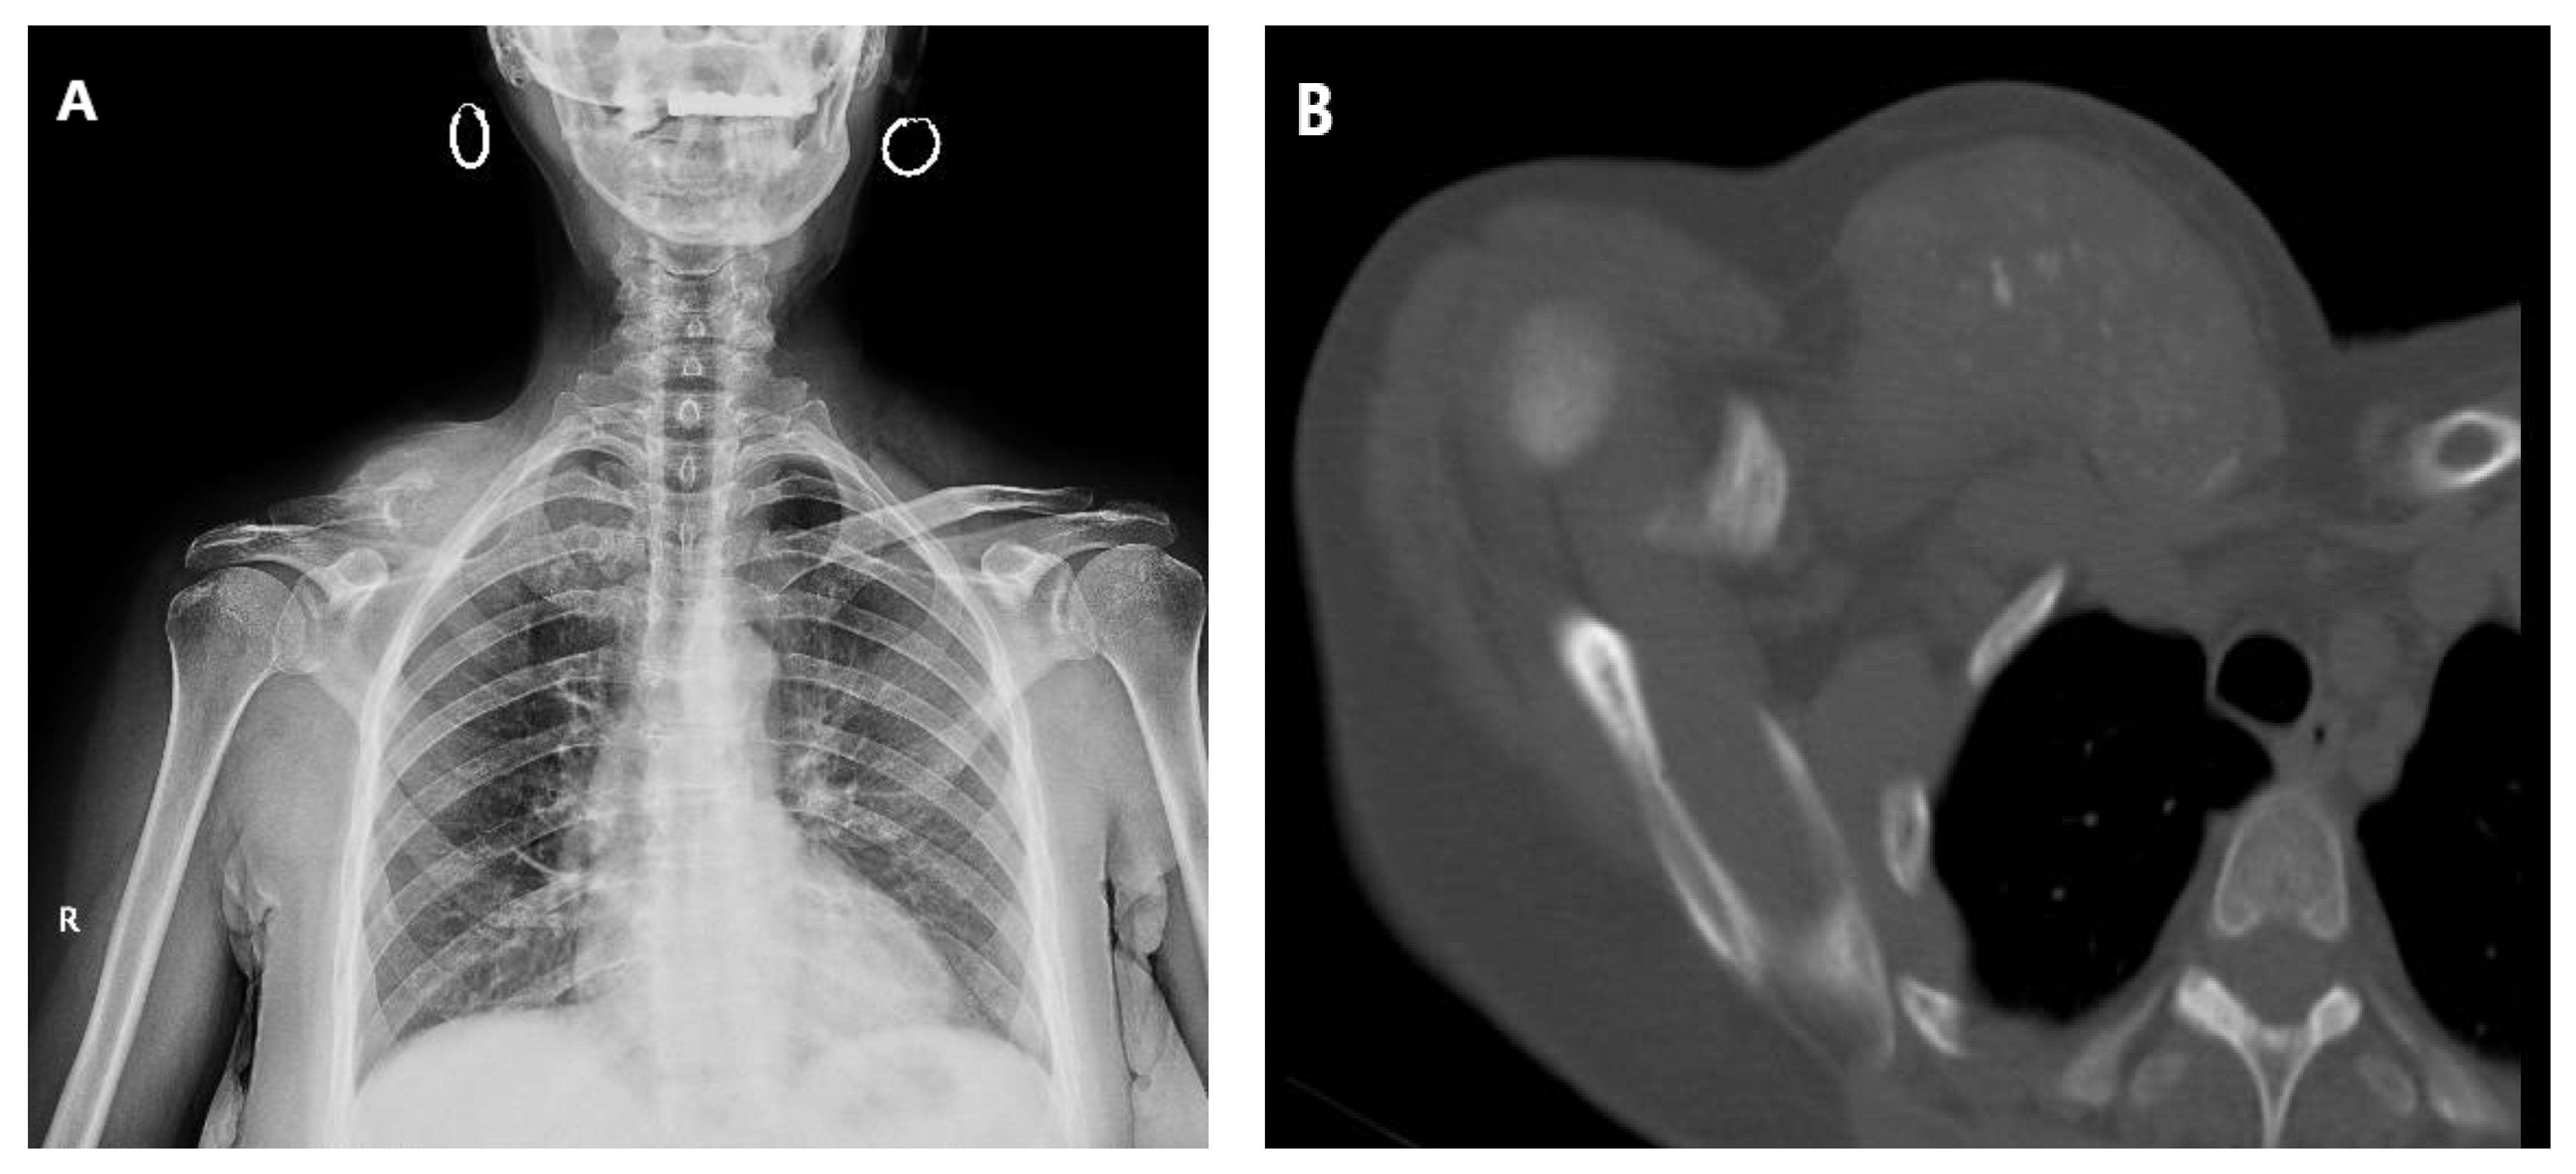

Figure 1.

Plain radiograph (A) and tomography (B) revealing extensive locoregional clavicle metastasis in a 60-year-old female, secondary to cervix adenocarcinoma. The patient presented with multiple metastases at diagnosis.